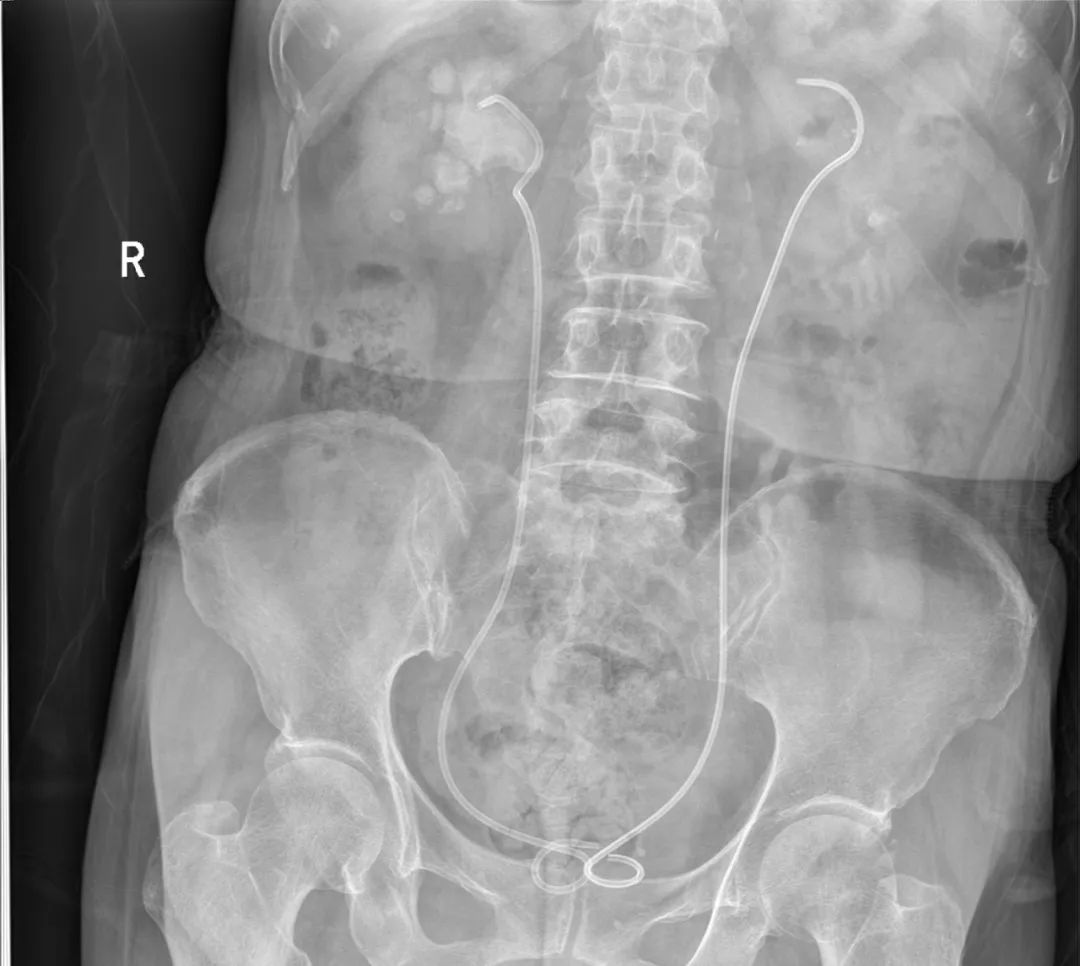

术后复查腹部平片

在经过精心手术前准备后,王卫东主任带领医院泌尿外科团队先后三次在全麻下行智能控压负压吸引经自然通道输尿管软镜碎石取石术,术后复查腹部平片,恢复好转后出院。